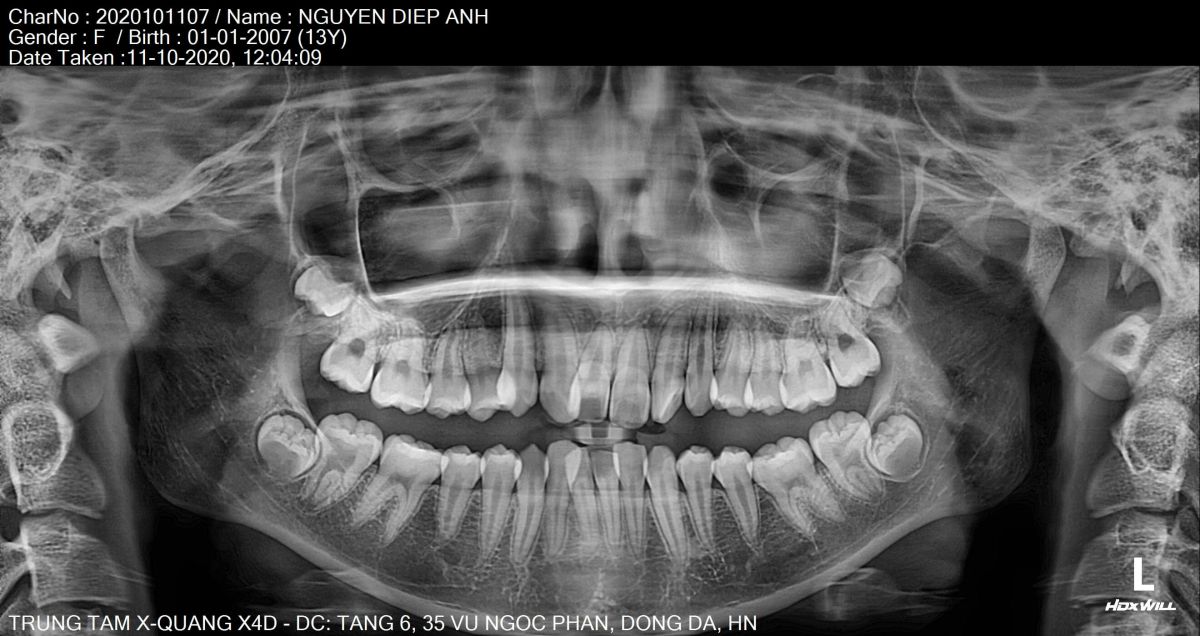

Bác sĩ chỉnh nha chuyên sâu trực tiếp xây dựng phác đồ dựa trên phim X-quang, hình ảnh 3D và phân tích khớp cắn, đảm bảo răng di chuyển đúng hướng – đúng lực – đúng thời điểm.